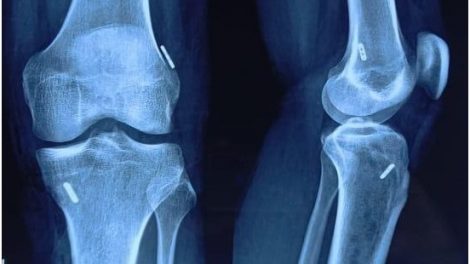

किसी भी एथलीट के लिए लिगमेंट की चोट उसके खेल कैरीअर को तबाह कर सकती है । अक्सर लिगमेंट की ऐसी चोटों के लिए अर्थ्रोस्कोपी (दूरबीन) शल्य क्रिया ही एक...